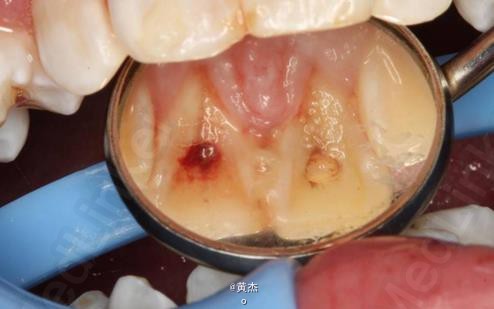

诊断:11、21根尖周炎。处理:11、21开髓无活力,大量血性渗出,根管无法测量。于是转诊口腔外科。术前和患者签知情同意书。给患者讲明外科手术有可能失败,最终拔除11、12、21的可能性。口腔外科处理:拔除13.。发现 11牙根几乎完全吸收、21唇侧牙根也被13牙冠压迫吸收到根中1/3。于是术中行11、21MTA根尖区封闭。12暂不做处理,观察半年后考虑进一步治疗方案。